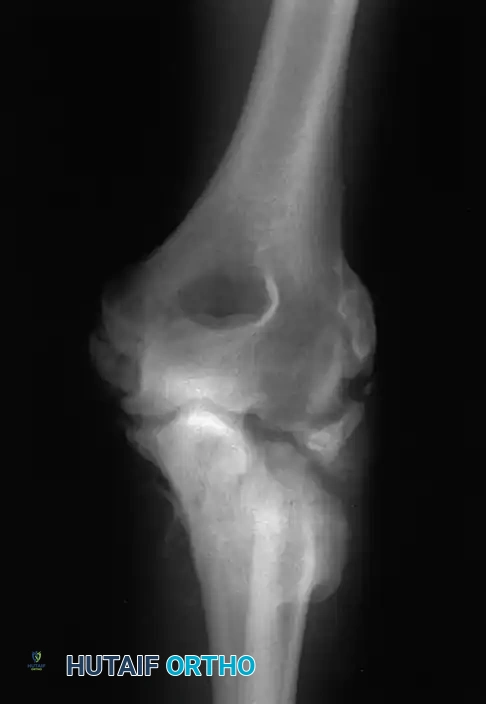

1. Posterior Approach with Olecranon Osteotomy

The trans-olecranon approach remains the gold standard for complex Type C fractures, providing unparalleled, direct visualization of the entire distal humeral articular surface.

Image

Fig. 7: Olecranon osteotomy approach. A chevron-shaped osteotomy is marked, initiated with an oscillating saw, and completed with an osteotome to preserve subchondral bone interdigitation.